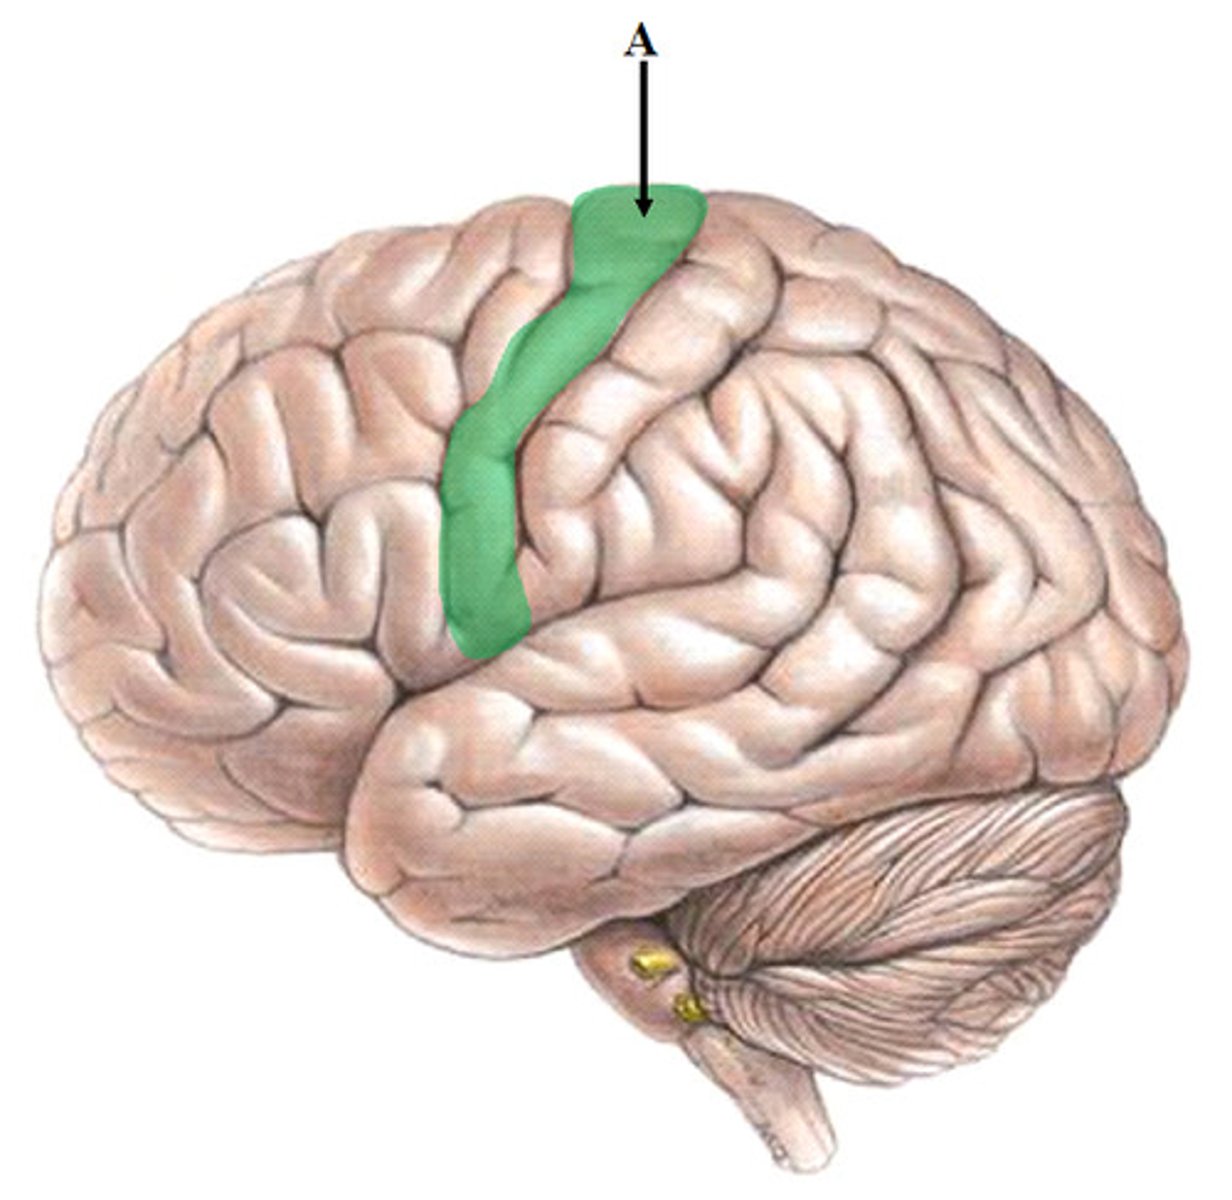

central sulcus

precentral gyrus

postcentral gyrus